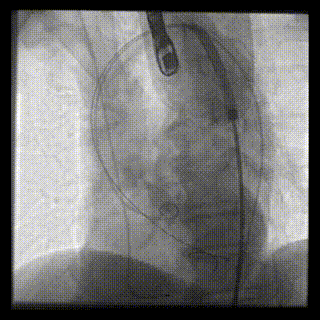

主动脉根部造影

22mm球囊预扩

输送器顺利过弓跨瓣

瓣环零位定位释放

第一次释放到工作位

工作位造影位置偏深

完全回收再次定位

第二次释放到工作位,位置理想

瓣膜完全释放

瓣膜完全释放后造影

外周造影